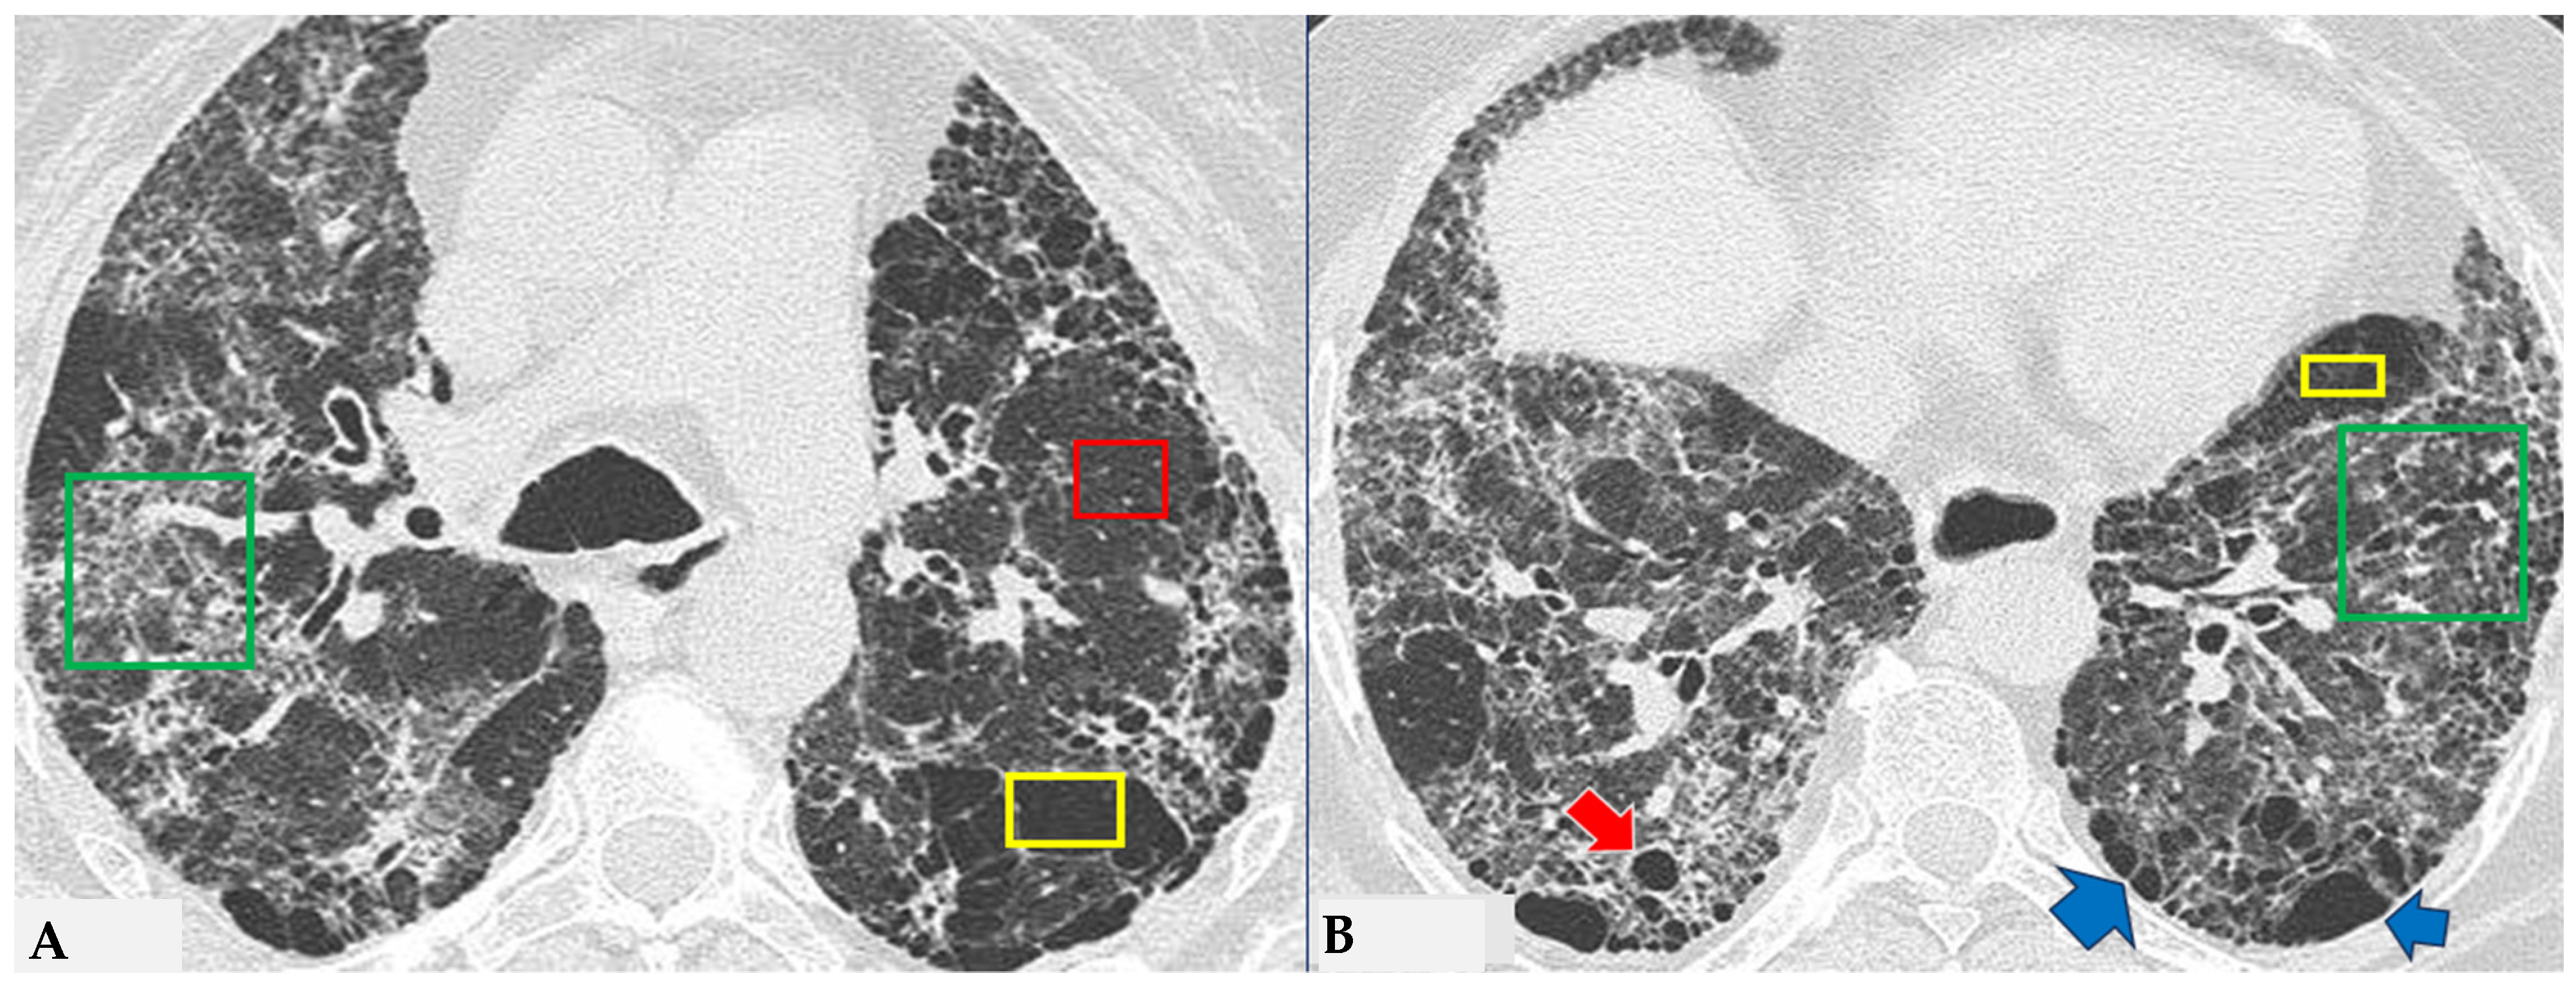

HRCT of the chest and magnification areas of RLL and LUL in FHP. Three-density pattern with lobular areas of reduced attenuation in both lungs (magnification images), overlapping with areas of increased density where distinct fibrotic alterations are evident, characterized by intra- and inter-lobular thickening with traction bronchiectasis and bronchiolectasis (red box). In certain patients, the absence of typical HRCT fibrotic features leads to their classification as “pattern compatible with FHP”. Suggestive elements of this pattern are fibrosis with a mixed central and peripheral distribution (Figure 7) and the fibrotic pattern with basal predominance (Figure 8).

Figure 7.

FHP with small areas of GGO related to acute exacerbation: axial chest HRCT scan. HRCT pattern characterized by mild amorphous GGO components in the upper lobes (red box), predominantly centrally located, with sectoral signs of interface and anterior asymmetric reticulations. Minimal traction bronchiolectasis coexists (A); subcarinal scan reveals GGO with moderate distortion, septal thickening and alterations predominantly bronchocentric in distribution (green box in (B)). The changes exhibit a “patchy” distribution with areas of mosaic attenuation.